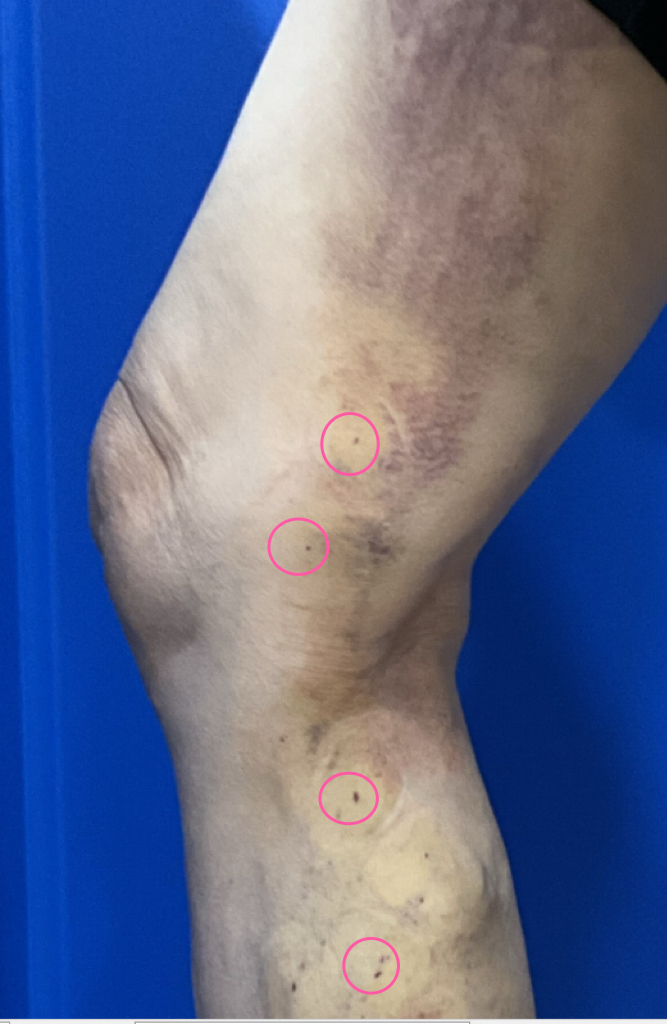

After

2. 이음하지외과의 디테일: 바늘 구멍의

기적

이 정도 크기의 혈관을 수술할 때,

숙련되지 않은 경우 절개창이

커질 수밖에 없습니다.

하지만 이음하지외과는 다릅니다.

포인트 미세수술:

수술 자국을 최소화하기 위해

바늘 구멍 크기의 미세 수술을 통해 돌출된

혈관을 하나하나 세밀하게 수술했습니다.

3. 수술 후 4일째: 감쪽같이 사라진 혈관

수술 후 4일이 지난 모습입니다.

그렇게 심하게 튀어나와 있던 손가락 굵기의

혈관들이 감쪽같이 사라졌습니다.

사진을 자세히 보셔도 바늘 구멍 정도의 작은

흔적 외에는 수술 자국을 찾기 어려울

정도입니다.

4일 만에 매끈해진 다리를 확인하신

환자분은 물론, 곁에서 지켜보신 자녀분께서

"이렇게 작은 구멍으로 그 굵은 혈관들이 다

없어지다니 정말 신기하다."

며 무척 놀라고 기뻐하셨습니다.